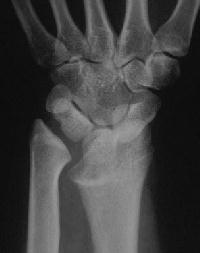

And the left side, preop:

And postop: Here, an inadequate ulnar gap led to heterotopic bone formation which almost resulted in a pseudarthrosis.